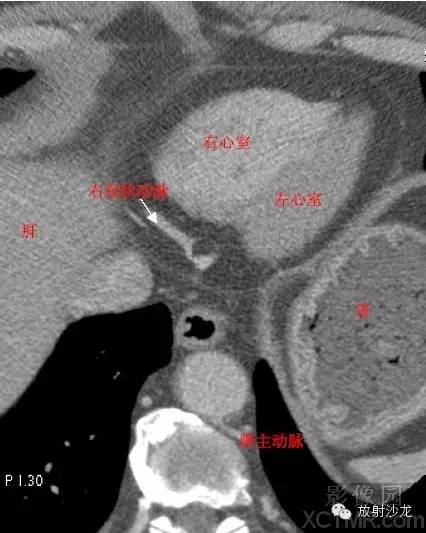

RA -Right Atrium右心房

LV -Left Ventricle左心室

RV -Right Ventricle右心室

D. Aorta-Descending Aorta降主动脉

RCA -Right Coronary Artery 右冠状动脉